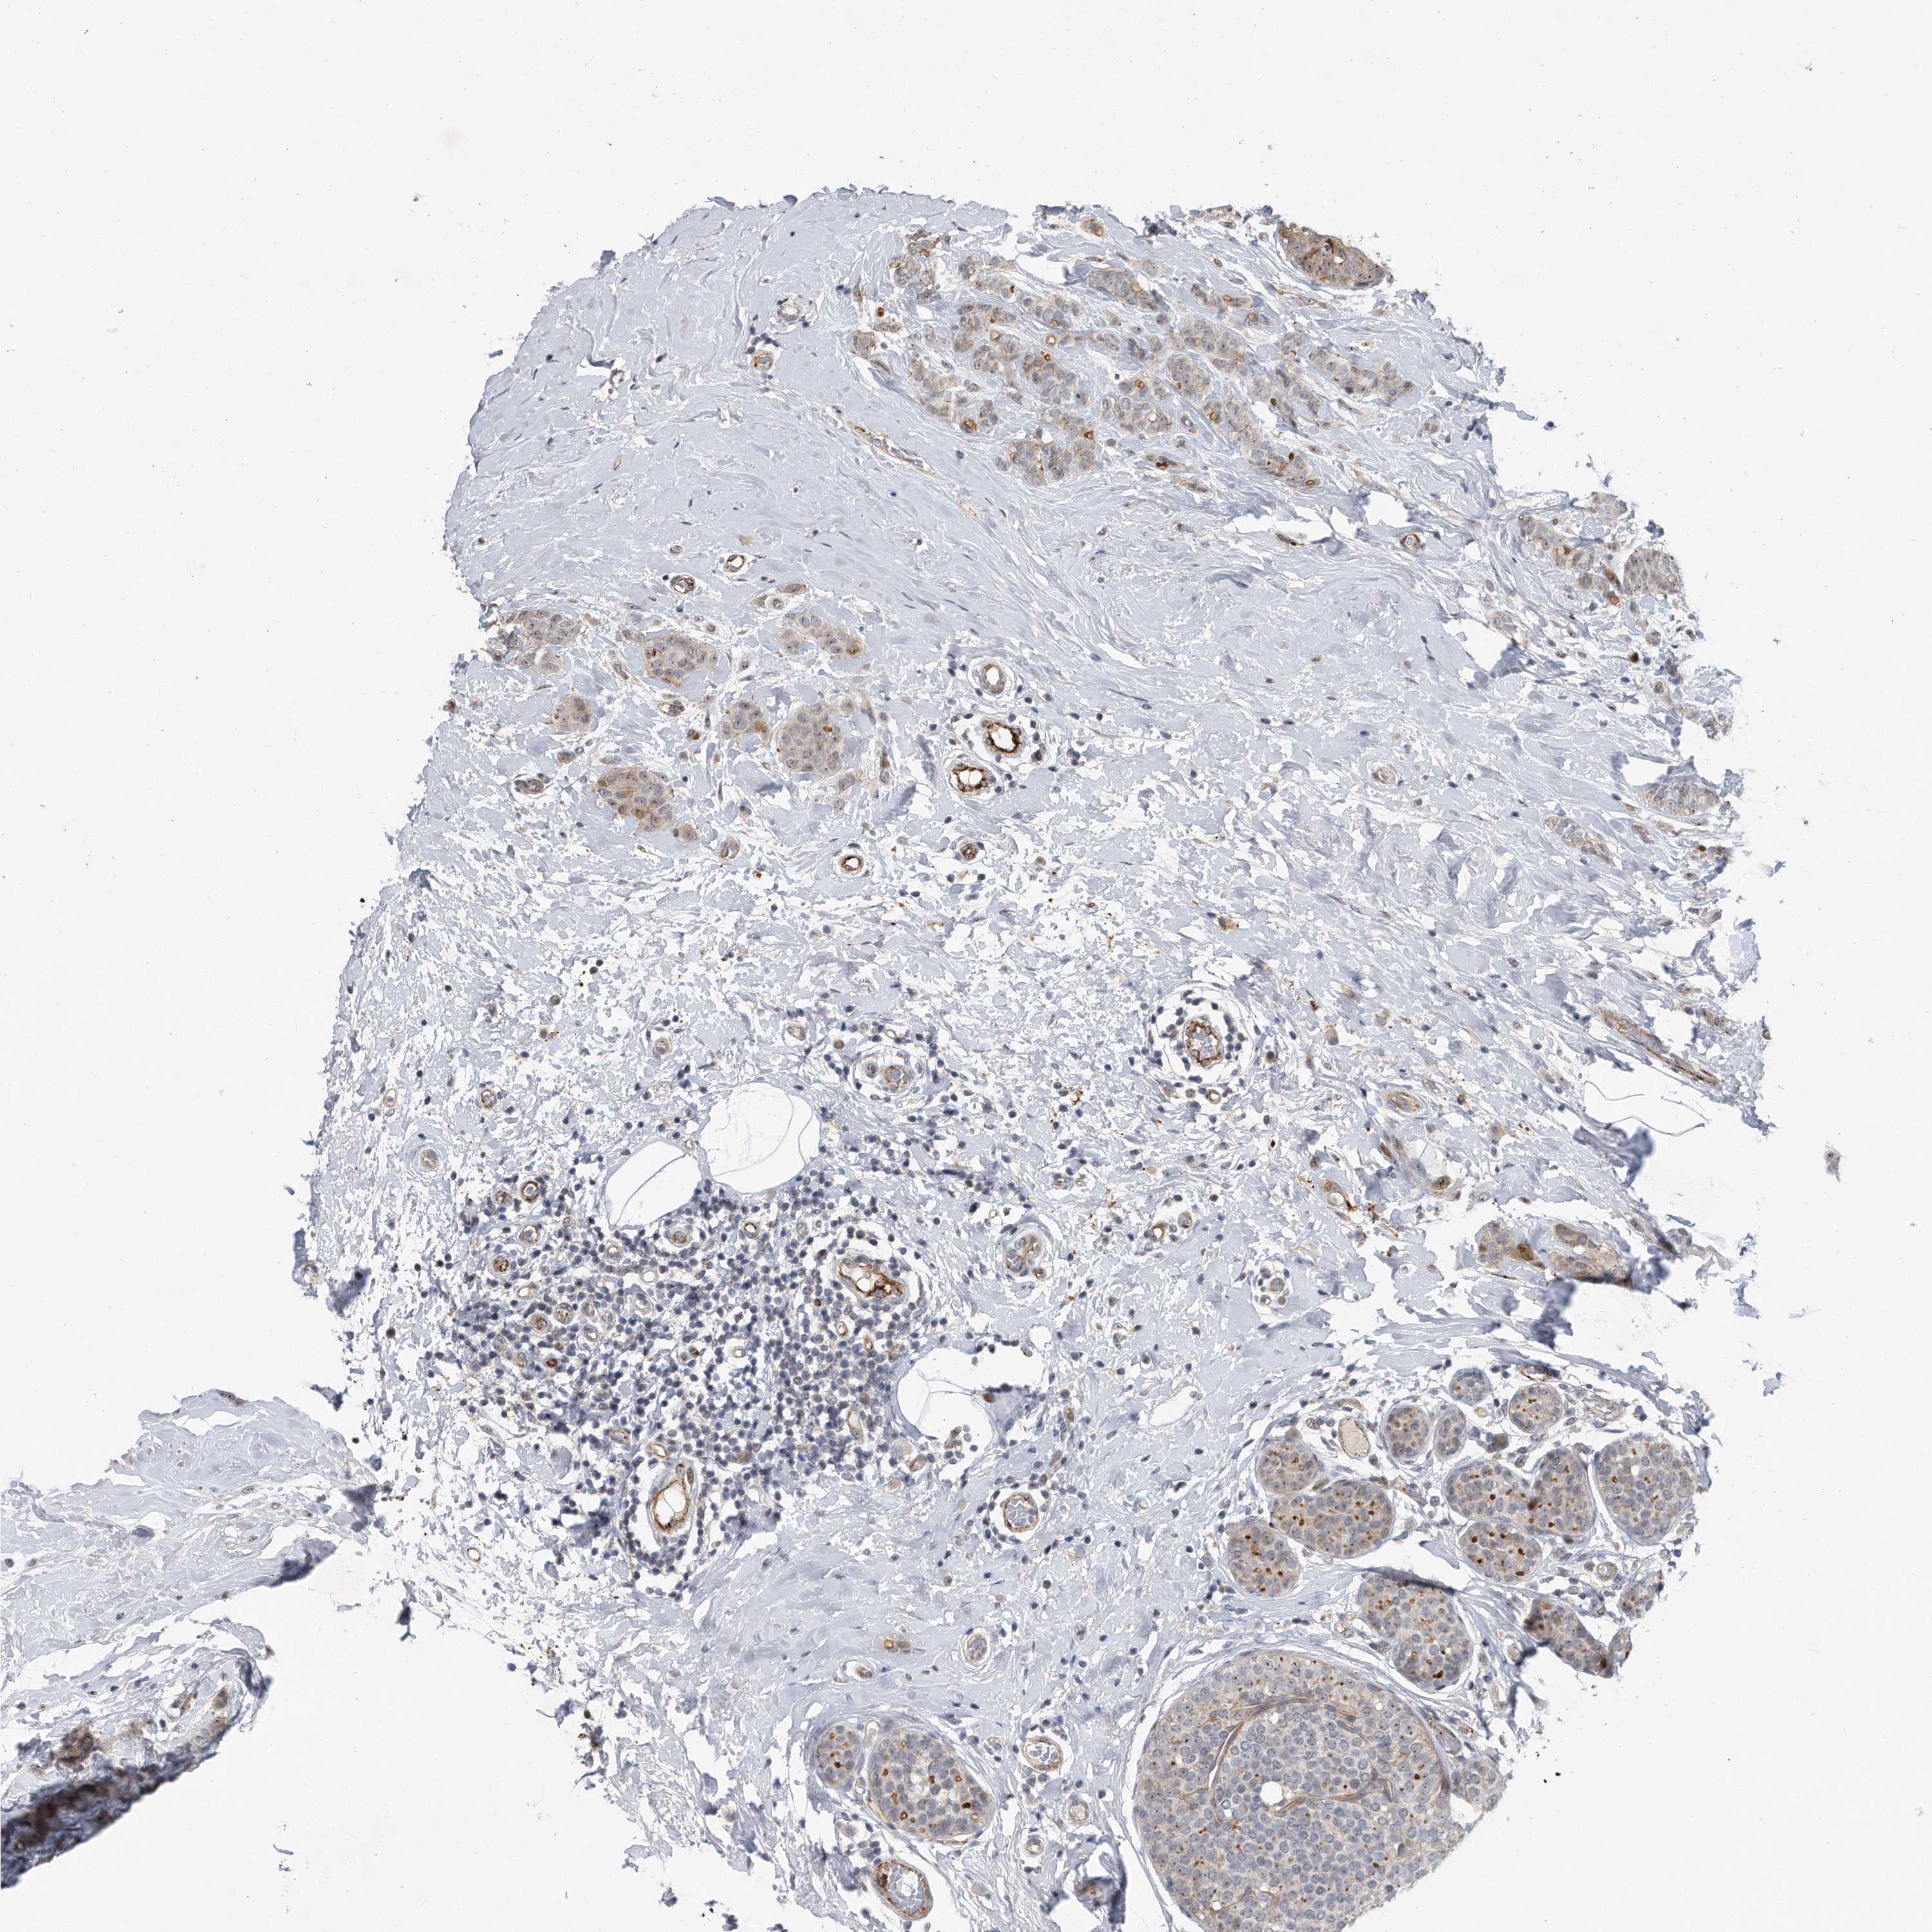

CANCER BREAST CANCER Show tissue menu

BRCA TCGA BRCA VALIDATION PROTEIN EXPRESSION

ANTIBODIES

AND

VALIDATION